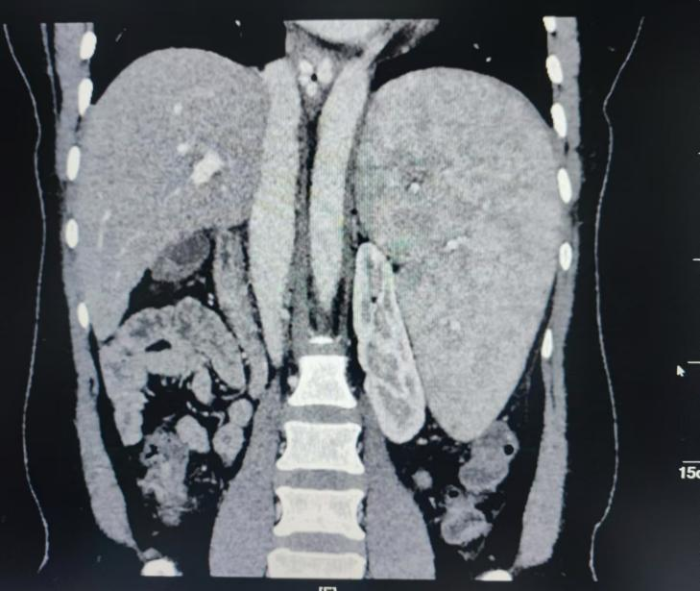

患者转入肝胆胰脾外科后,肝胆胰脾外科杨志坚副主任医师根据患者门静脉高压侧枝循环扩张,为尽可能减少操作步骤从而减少出血,采用腹腔镜下原位隧道法脾脏全切术,无需解剖脾门血管减少出血风险结合应用血液自体回收技术顺利完成手术。手术后第一天,付出白细胞、红细胞、血小板数已呈现上升趋势。围手术期通过应用加速康复外科以及肝硬化腹水全流程管理,患者在术后无明显腹水,并于6天后康复出院。

据南溪山医院肝胆胰脾外科副主任杨志坚介绍,脾切除术既属于治疗手段,又属于预防手段。一方面去除了肿大的脾脏以消除脾功能亢进,另外方面又离断了食管胃脾区的门体侧支以预防食管胃底静脉曲张出血。腹腔镜手术因巨脾占位效应,导致手术操作空间狭小,加之脾脏血管异常扩张,血管变薄极易造成大出血导致手术失败,对手术医生要求较高。相比开放手术,腹腔镜下手术的切口面积小,创伤少,有助于缓解疼痛降低机体炎性反应,对患者免疫力影响较小。腹腔镜操作模式下,患者肠管内部环境稳定而且术中不会对肠管产生严重挤压,有助于病情短时间内恢复。

蒋女士腹部伤口

传统开腹伤口